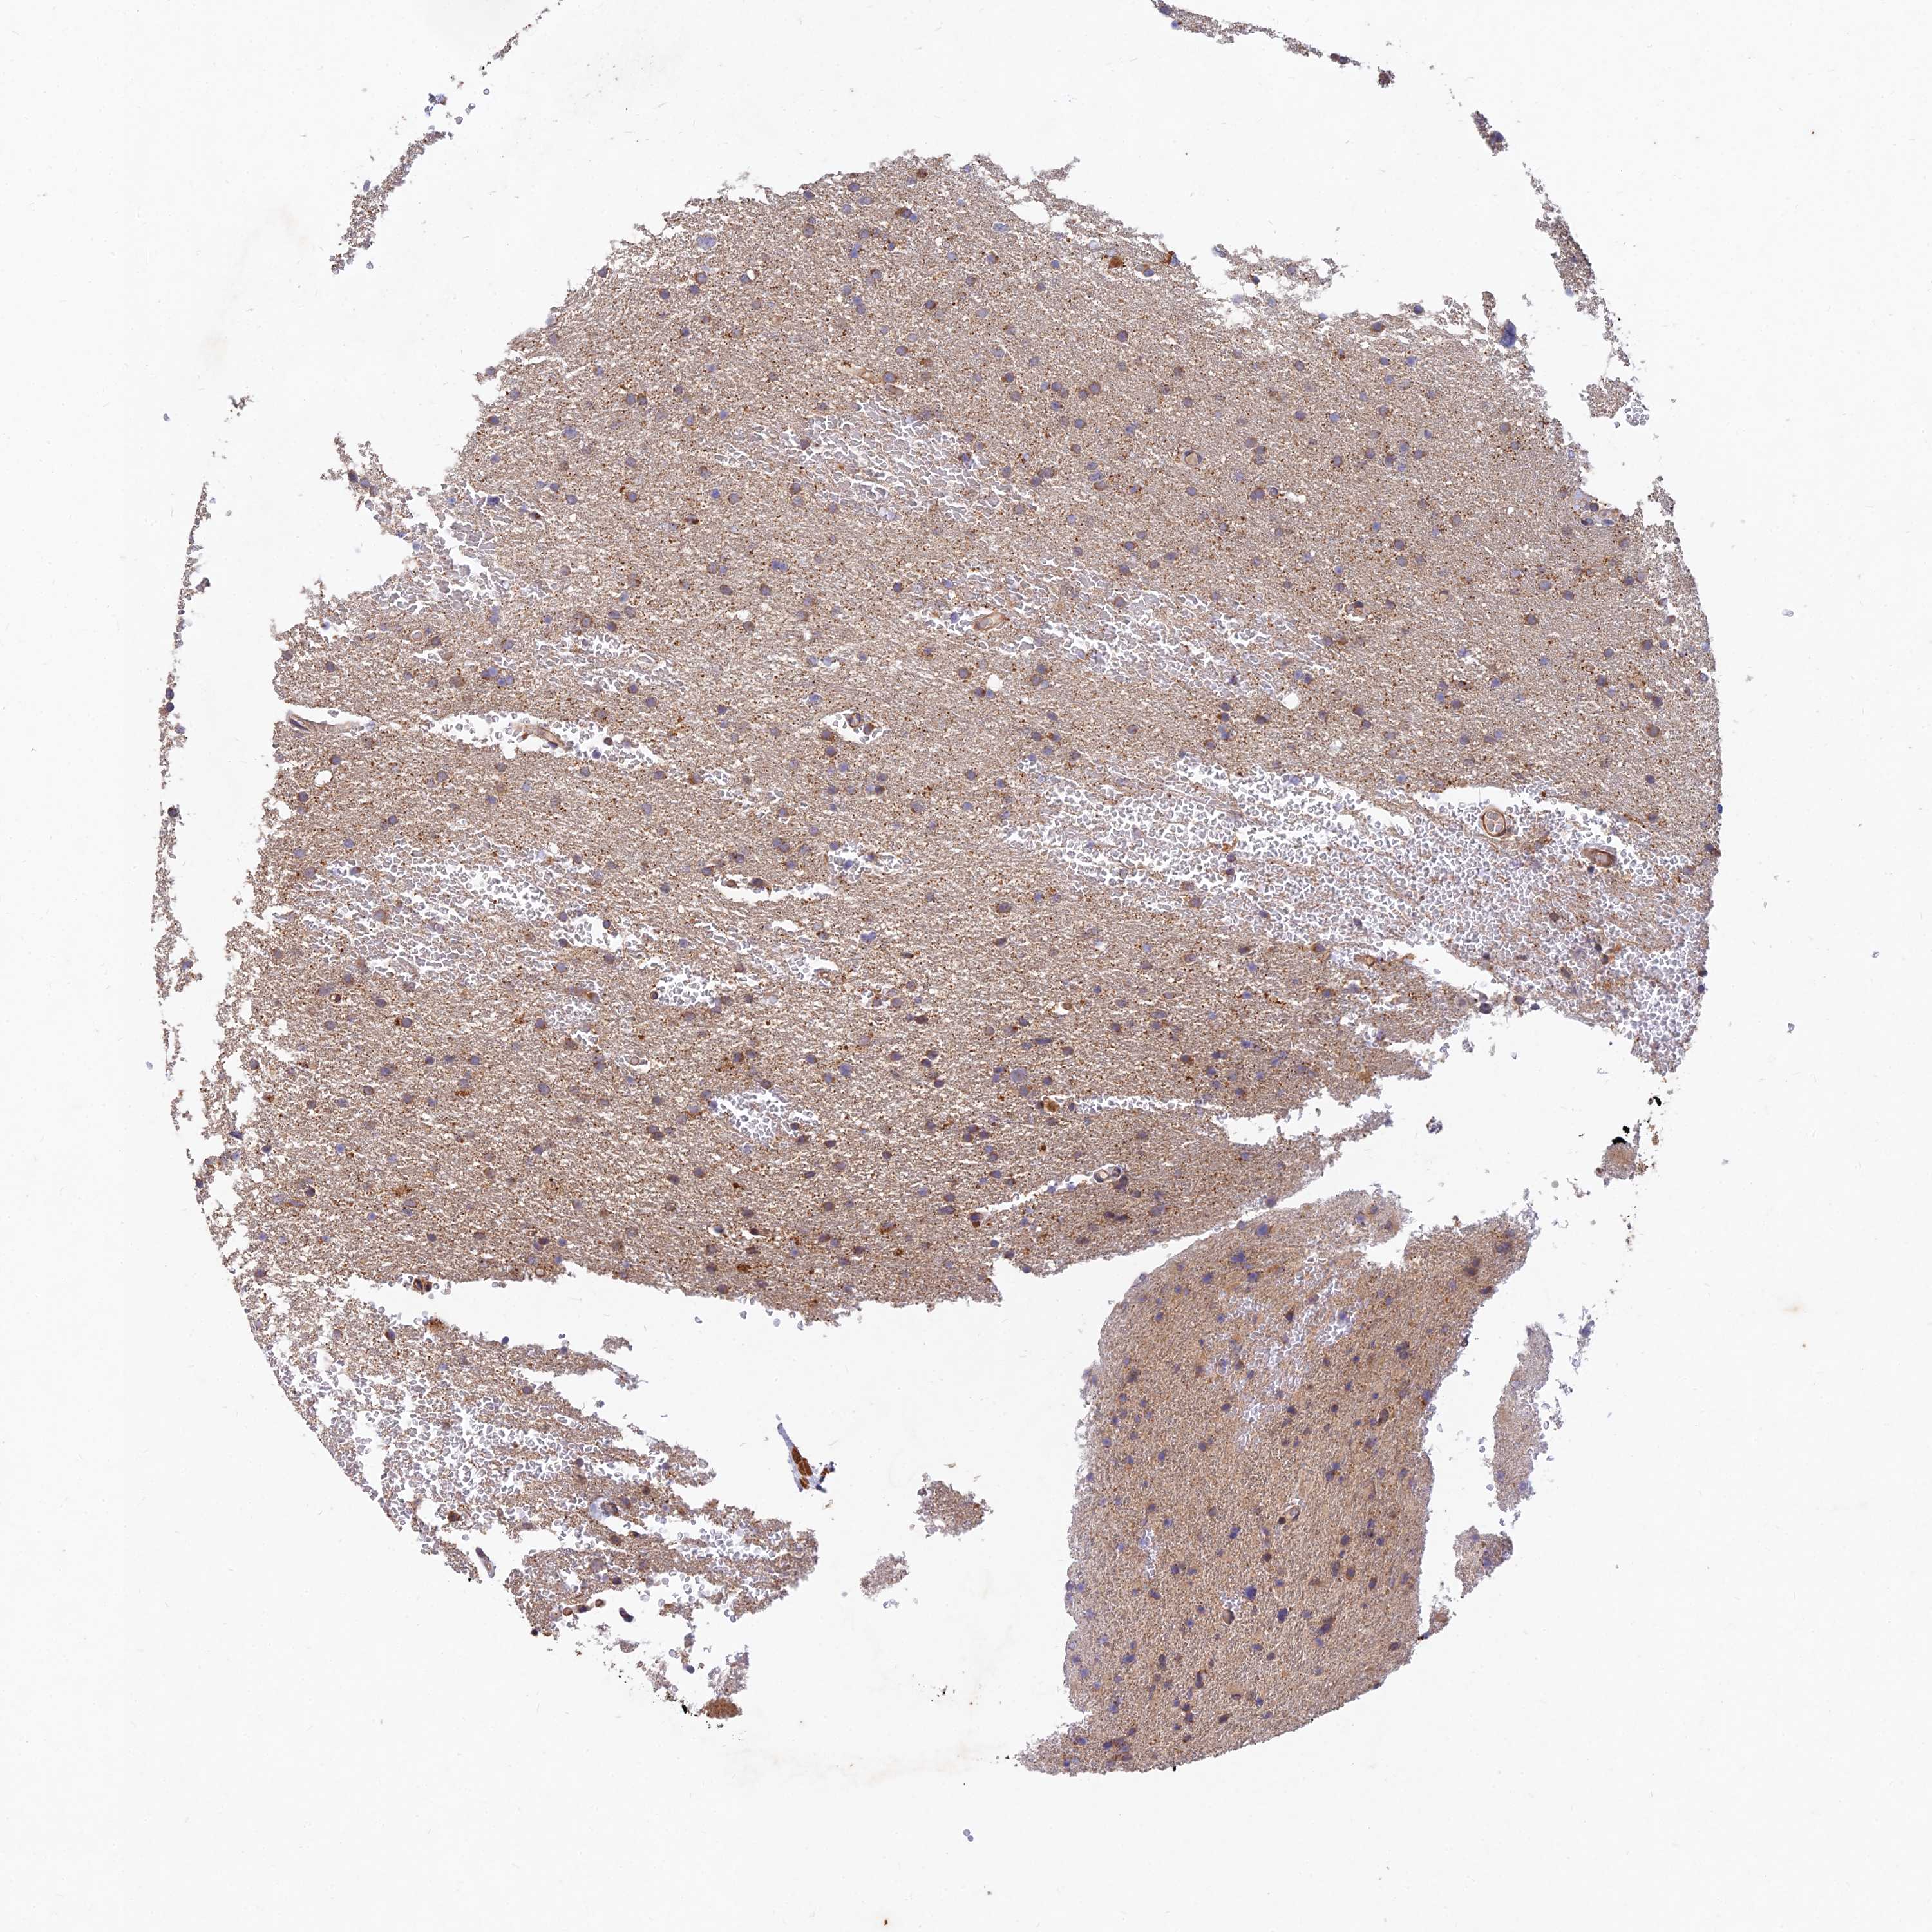

GLIOMA - Protein expressioni

A mouse-over function shows sample information and annotation data. Click on an image to view it in a full screen mode. Samples can be filtered based on level of antibody staining by selecting one or several of the following categories: high, medium, low and not detected. The assay and annotation is described here.

Note that samples used for immunohistochemistry by the Human Protein Atlas do not correspond to samples in the TCGA dataset.

Antibody stainingi

Antibody staining in the annotated cell types in the current human tissue is reported as not detected, low, medium, or high, based on conventional immunohistochemistry profiling in selected tissues. This score is based on the combination of the staining intensity and fraction of stained cells.

Each image is clickable and will lead to virtual microscopy that enables deeper exploration of all samples and also displays staining intensity scores, fraction scores and subcellular localization as well as patient and tissue information for each sample.

Antibody HPA039708

Antibody HPA040038

Staining

High

Medium

Low

Not detected

Intensity

Strong

Moderate

Weak

Negative

Quantity

>75%

75%-25%

<25%

None

Location

Nuclear

Cytoplasmic/membranous

Cytoplasmic/membranous,nuclear

Glioma, malignant, High grade

Glioma, malignant, Low grade